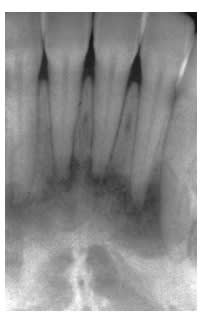

Ce qui est intriguant, sensibilité de capteur ? C'est qu'on a pas une limite bien définie, on a l'impression que les trabeculations osseuses entrent dans l'image radio-claire, Sethef connait mieux son capteur que nous. Le ligament parodontal semble peu, pas affecté, c'est "propre comme image".

Je te confirme que je vois une continuité du ligament autour de l'apex, alors qu'il devrait avoir disparu. Ca fait partie de mes doutes.

Sur les laterales on voit 2 contours ligamentaires, cela ne veut pas forcément dire que ces dents présentent 2 canaux mais des incisives mandibulaire à deux canaux c'est loin d'être rare et ces dents sont celles qui présentent le plus haut taux d'échecs de traitement endodontique.

Des lésions d'origine odf auraient probablement causées également des résorptions qui ont un aspect plat assez caractéristique.